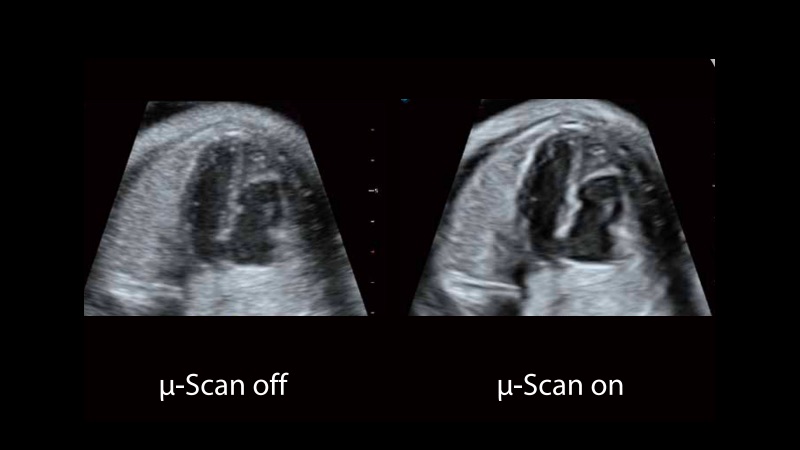

μ-Scan+新一代微米成像技术

新一代微米成像技术大大提高了器官和病变的可见性。高清对比度分辨率将抑制斑点噪声,同时保持真实的组织结构。